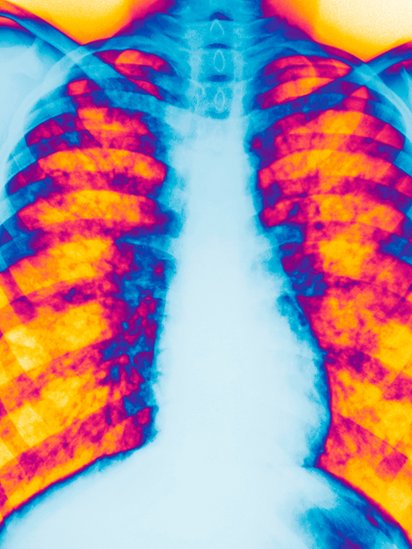

El paciente toma alrededor de 60 pastillas al día para ayudar a controlar la enfermedad, un mal genético que provoca la acumulación de flema en los pulmones, y que también puede afectar al páncreas y al tracto gastrointestinal.